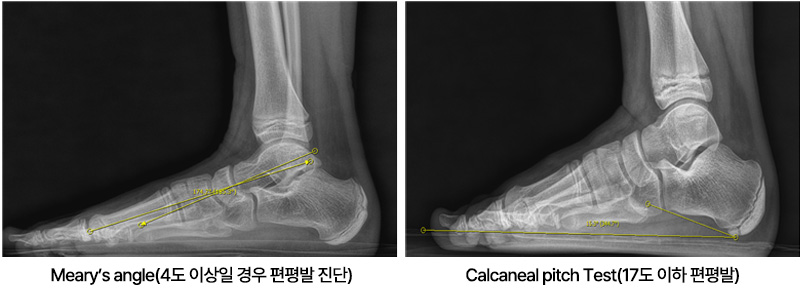

아킬레스 짦음증이 있는 아이들은 자주 발목이나 종아리가 아프다고 하며, 아픈 부위를 특정하지 못하고 다리가 아프다고 하며 내원합니다. 가끔은 발 뒤꿈치를 들고 걷는다고 하거나 까치발로 걷는다고 내원하기도 합니다. 걷는 자세는 주로 팔자걸음에 상체를 흔들면서 걷습니다. 이런 아이들은 좀 더 크면 무릎이나 허리를 아파하기도 합니다. 어린아이들의 경우에는 X-ray 등에도 이상 소견이 보이지 않아 주로 성장통이라고 오진을 받기도 합니다. 저희 병원에서는 현재 이에 대한 연구를 진행하고 있으며, 이런 아이들의 대략 60% 정도에서 비만이 있고, 이러한 비만아이들은 골연령이 약 1.5세 정도 증가하게 되어 성인예측키에서 약 3~4cm 정도의 손실이 발생합니다. (이상은 본원에서의 미발표 연구결과입니다)

아킬레스 짧음증 : 자주 발목이나 종아리 통증을 호소, 아픈부위를 특정하지 못하며 다리가 아프다고 호소. 9세 이후에도 까치말로 걷는등의 증상호소.